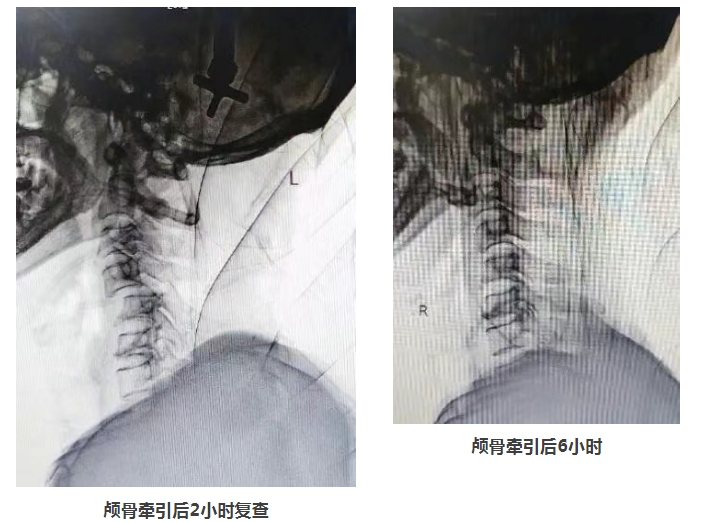

临床上颈椎骨折患者病情轻重不一,有人甚至当场死亡,市一院创伤中心当班的熊军委主诊医师团队在详细了解病情后,立即将患者收入创伤中心重症病房(TICU),并当机立断实施颅骨牵引、脱水、营养神经等一系列关键治疗措施,稳定病情,将患者从死亡线上拉回来。 颅骨牵引常作为颈椎损伤非手术治疗的重要方法,适用于颈椎骨折和脱位患者,尤其是骨折、脱位伴有脊髓损伤者,存在不小的操作难度。一方面,颅骨解剖结构复杂,进针时必须精准掌握部位与深度,稍有差池就可能损伤硬脑膜、血管和神经等重要结构;另一方面,牵引装置安装的精准度要求极高,牵引弓位置、牵引绳方向和张力都要恰到好处,否则会导致颈椎二次损伤等不良后果。此外,颅骨牵引还面临着穿刺部位感染、出血,以及牵引中神经损伤、肌肉萎缩等并发症风险,处理这些问题需要术者具备丰富临床经验。 4天后,在医生们密切复查、时刻关注下,沈大爷病情稍有稳定。颅骨牵引的成功开展,为大爷后期手术创造了有力条件。创伤中心迅速联合院内多学科专家,开展综合诊疗会诊讨论(MDT)。专家们反复研讨、严谨评估,考虑到患者高龄、颈椎脱位十分严重,不适合行脊柱内镜、人工椎间盘等手术,决定由名医工作室专家吕志华主刀,为沈大爷施行颈椎前路减压融合内固定术的开放型手术。 颈椎手术作为脊柱骨科难度系数最高的手术之一,需要对颈部脊髓充分减压,手术操作难度系数大、技术及经验要求高,而颈椎前路手术因靠近气管,需要手术区域完全止血,即使一个小血管渗血都有可能导致颈部血肿压迫气管而危及生命。 吕志华凭借精湛的医术和丰富的经验,精准操作每一个步骤,直接解除脊髓前方的压迫,同时通过植入融合器及内固定装置,恢复颈椎的稳定性。手术历时2小时30分钟,成功完成。 在市一院创伤中心医护人员夜以继日的精心治疗与无微不至的悉心照料下,沈大爷四肢麻木及活动受限明显好转,在颈托保护下逐步可以下床活动。创伤中心骨科组医师最终帮助这位患者成功战胜了这场严重创伤,重新站起来了! 创伤中心负责人施剑明提醒广大市民朋友,在日常生活中要注意保护颈椎,一旦出现颈部疼痛、活动受限、四肢无力等症状,应引起重视。当发生颈部损伤并有颈部以下感觉、运动障碍时,请及时送医并注意谨慎搬运患者,避免严重后果的发生。